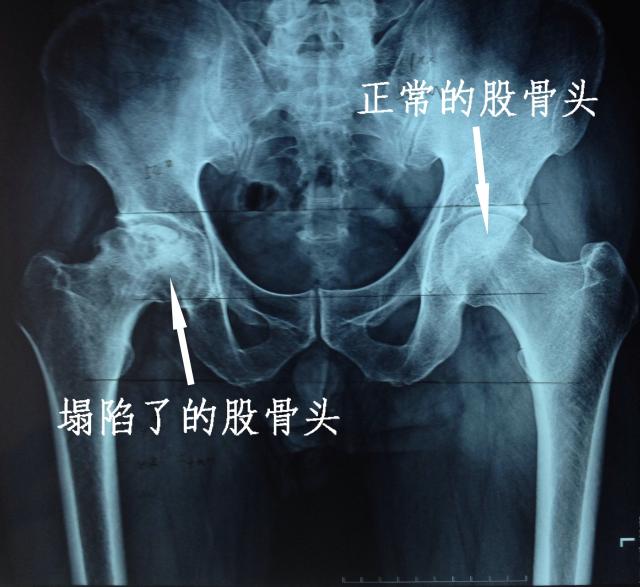

來自北京的股骨頭壞死保守治療專家常榮主任說:股骨頭壞死主要是因為髖關節血運不暢引起的,治療股骨頭壞死,重點就是要解決血運循環的問題。